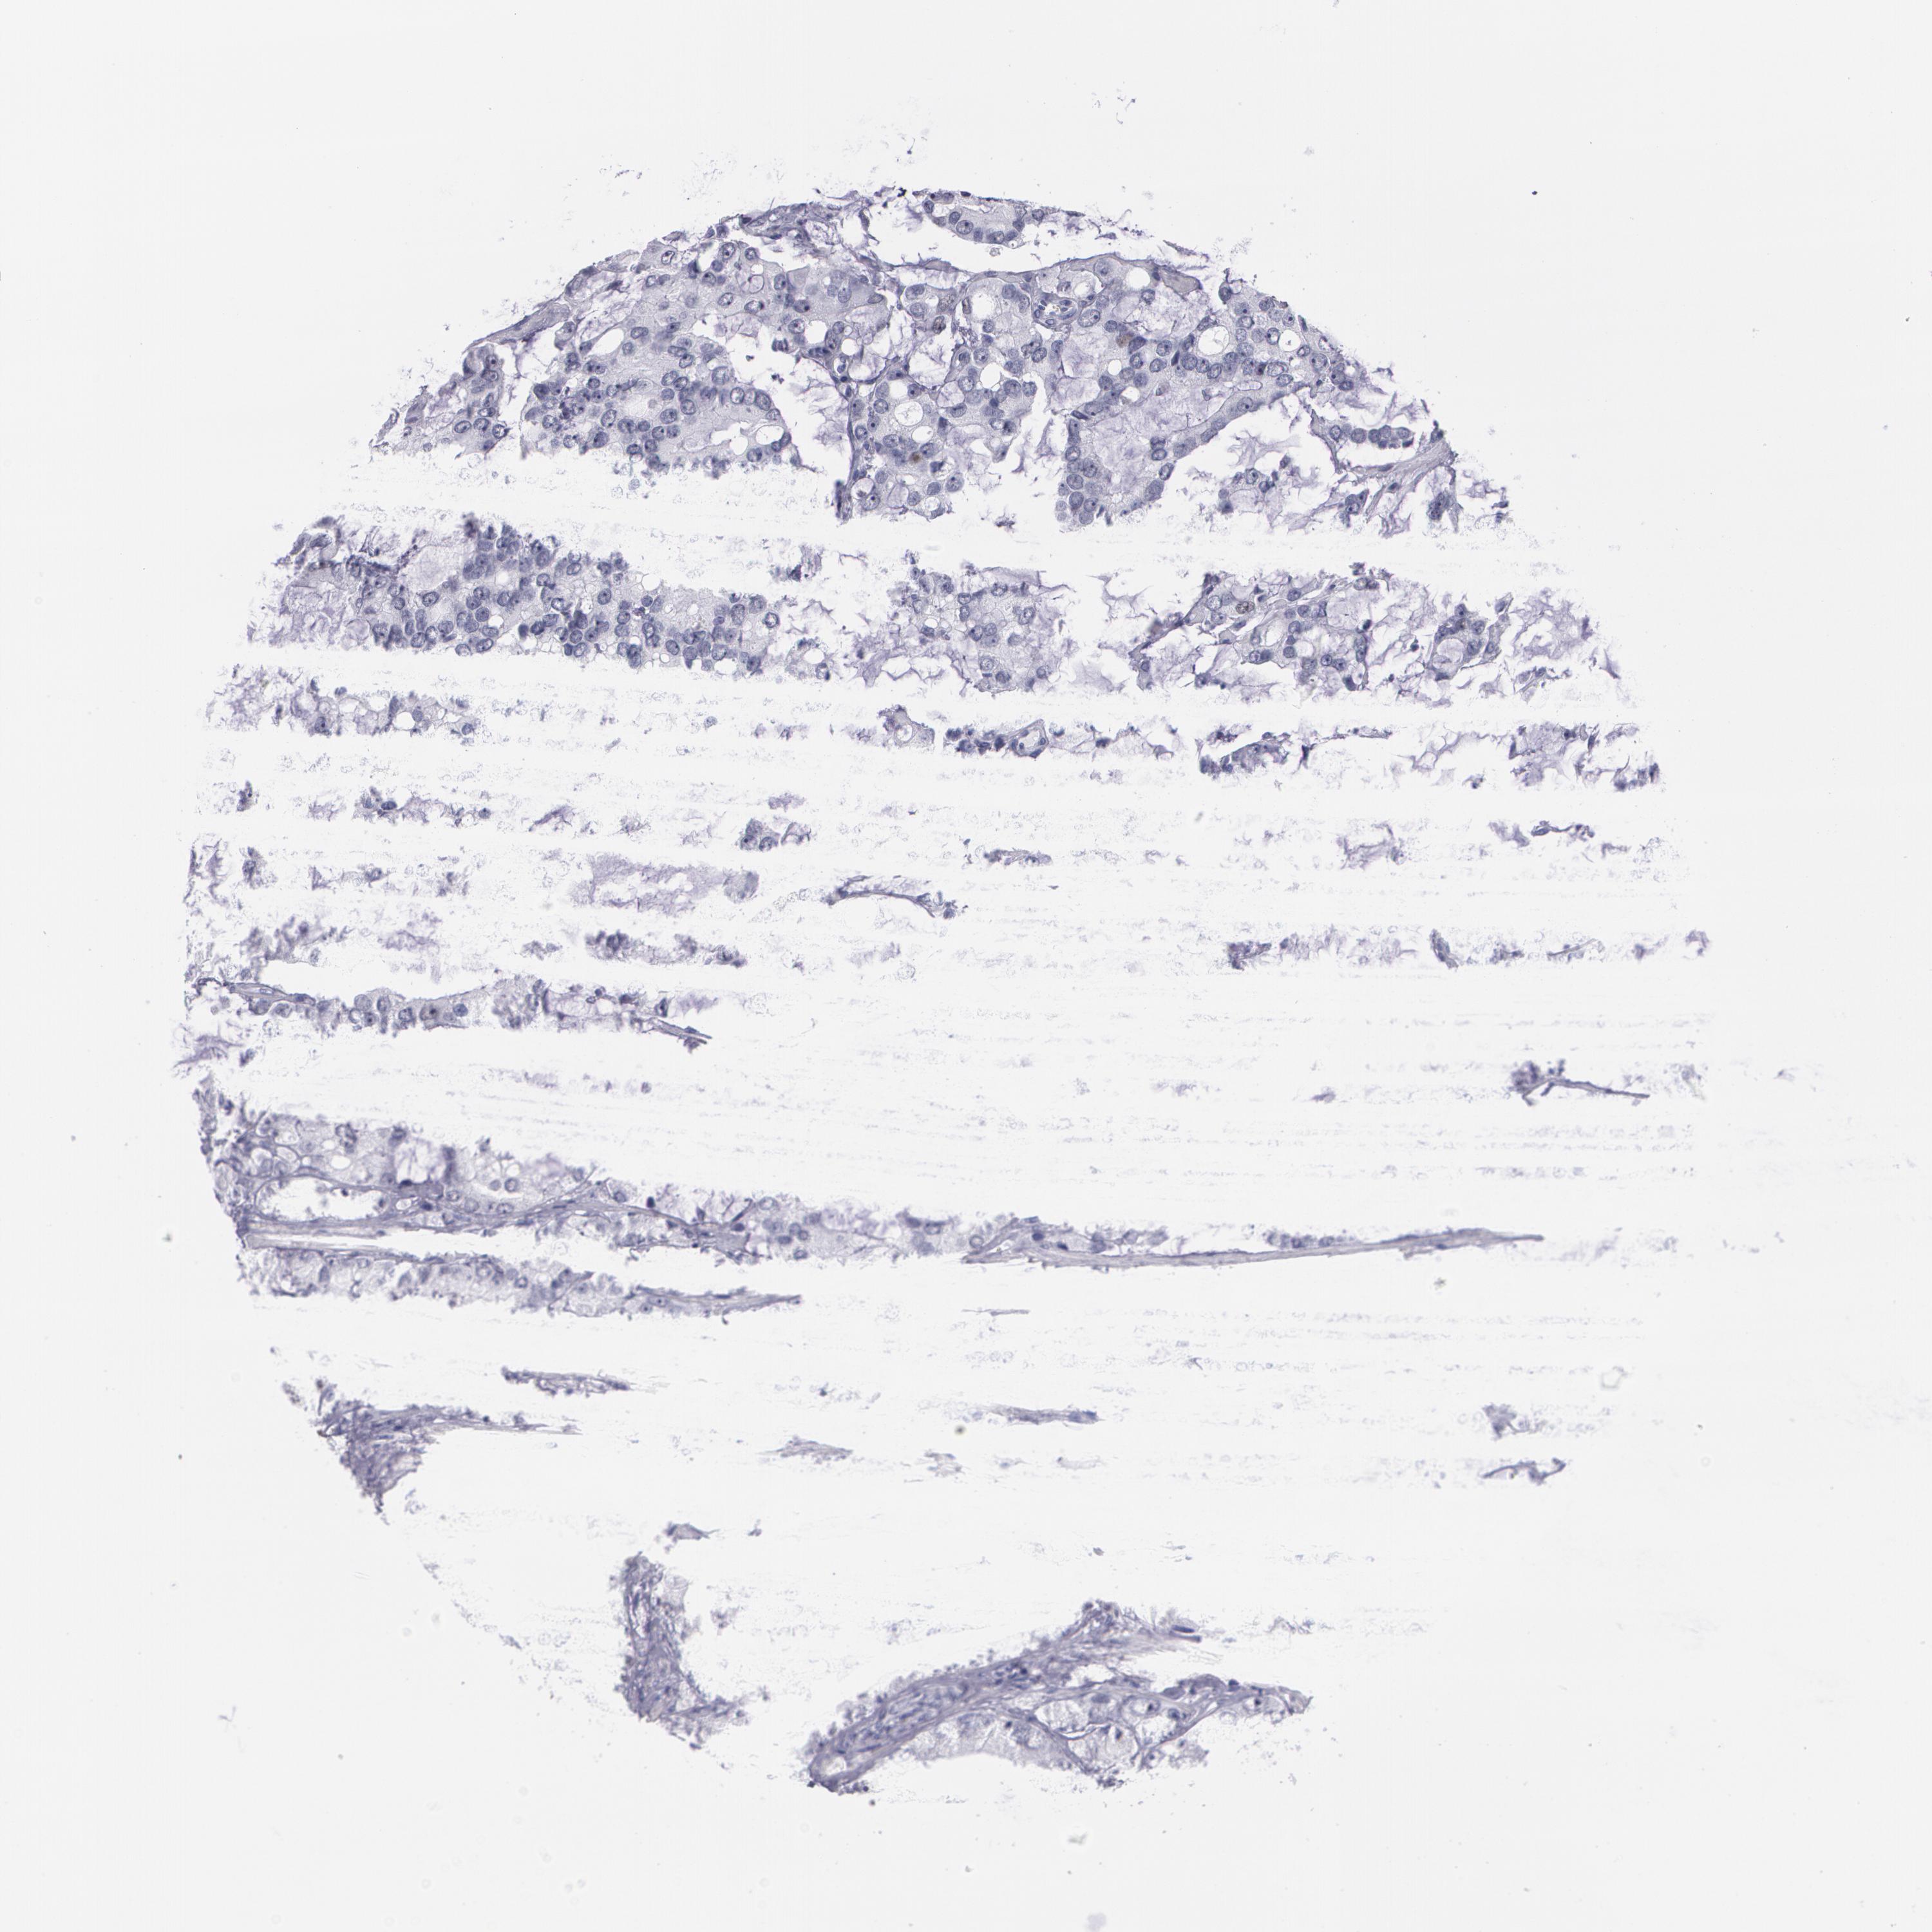

PROSTATE CANCER - Protein expressioni

A mouse-over function shows sample information and annotation data. Click on an image to view it in a full screen mode. Samples can be filtered based on level of antibody staining by selecting one or several of the following categories: high, medium, low and not detected. The assay and annotation is described here.

Note that samples used for immunohistochemistry by the Human Protein Atlas do not correspond to samples in the TCGA dataset.

Antibody stainingi

Antibody staining in the annotated cell types in the current human tissue is reported as not detected, low, medium, or high, based on conventional immunohistochemistry profiling in selected tissues. This score is based on the combination of the staining intensity and fraction of stained cells.

Each image is clickable and will lead to virtual microscopy that enables deeper exploration of all samples and also displays staining intensity scores, fraction scores and subcellular localization as well as patient and tissue information for each sample.

Antibody CAB002973

Antibody CAB039238

Antibody CAB039239

Antibody CAB072876

Staining

High

Medium

Low

Not detected

Intensity

Strong

Moderate

Weak

Negative

Quantity

>75%

75%-25%

<25%

None

Location

Nuclear

Cytoplasmic/membranous

Cytoplasmic/membranous,nuclear

Adenocarcinoma, Low grade

Adenocarcinoma, Medium grade

Adenocarcinoma, High grade

Adenocarcinoma, NOS